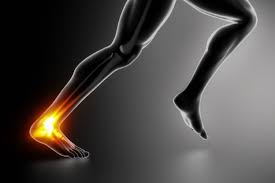

Αδάμ Αθανάσιος, MD, FICS Ορθοπεδικός Χειρουργός, συνεργάτης Euromedica-Γενικής Κλινικής Θεσσαλονίκης Τηλ: 6974108266, 2310532666, 2310895191 Το στραμπούληγμα ή διάστρεμμα του αστραγάλου, όπως είναι η ιατρική ορολογία, είναι η συχνότερη Read More…

Η ρήξη του Αχίλλειου τένοντα αποτελεί μια συχνή, συνήθως αθλητική κάκωση. Τις τελευταίες δυο δεκαετίες τα ποσοστά έχουν αυξηθεί αρκετά κυρίως λόγο της αύξησης των αθλητικών δραστηριοτήτων στις μεγαλύτερες Read More…